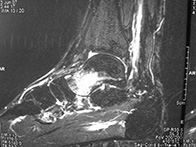

Eine Stressfraktur (Stressbruch) ist ein inkompletter Bruch eines Knochens und kann jeden Knochen des Fußes betreffen. Eine Stressfraktur entsteht meist durch wiederholte Überbelastung des betroffenen Knochens. Der Grund einer Stressfraktur kann eine generelle Fehlhaltung des Fußes sein. Wie die Stressfraktur können auch Knochenmarködeme durch Überbelastung, oder aber ohne ersichtliche Ursache entstehen. Stressfrakturen und Knochenmarködeme werden durch Einlagen, Ruhigstellung im Walker oder Gips und durch den Einsatz spezieller Medikation zur Ausheilung gebracht.

Ein Ganglion ist eine Zyste, welche mit gelatinartiger Flüssigkeit gefüllt ist. Die Diagnose eines Ganglions wird mit Hilfe des Ultraschalls oder einer MRT’s gestellt. Wenn das Ganglion Schmerzen am Fuß bereitet, sollte es chirurgisch entfernt werden. Die Entfernung des Ganglions kann meist in lokaler Betäubung durchgeführt werden.